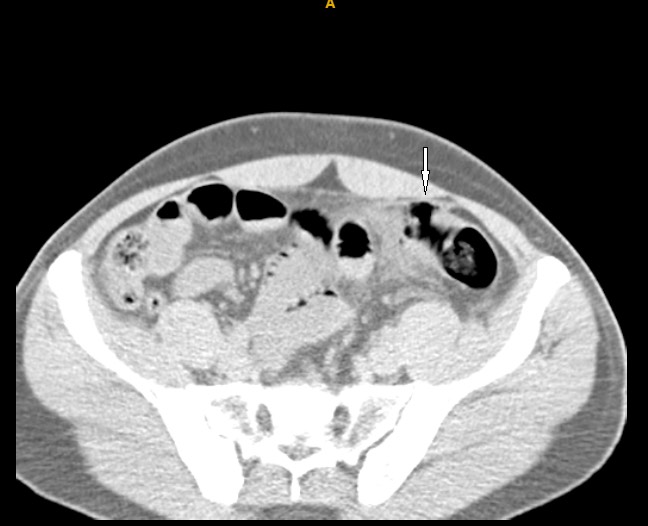

Bệnh nhân nam,54 tuổi nhập viện vì bị một cây gỗ đập vào vùng bụng dưới rốn cách nhập viện 5 giờ. Bệnh nhân đau nhiều vùng hố chậu trái, không sốt, không buồn nôn hay nôn mửa. Khám lâm sàng thấy bụng mềm, không có vết bầm tím trên thành bụng, hố chậu phải mềm hoàn toàn, ấn đau 1 vùng khoảng 10× 10cm vùng hố chậu trái, phản ứng thành bụng (±), tiểu tự chủ vàng trong. Xét nghiệm cận lâm sàng bình thường ngoại trừ bạch cầu tăng nhẹ 10.77 G/L neurophile  83%. X quang bụng đứng không có liềm hơi dưới cơ hoành (Hình 1), không có mức hơi dịch. Siêu âm bụng không có hơi tự do, không có dịch ổ phúc mạc.

Hình 1. X quang bụng khi vào viện không có liềm

hơi dưới cơ hoành